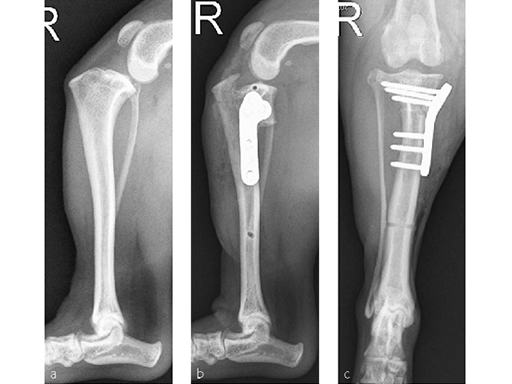

A Bichon Frise became acutely non weightbearing lame following running, with a tear of the cranial cruciate ligament.

The preoperative tibial plateau angle was 36. The jig pin diameter was 1.6 mm. A 10 mm TPLO saw blade was used to make the osteotomy while the jig was in place. A 2.0 mm Synthes TPLO Plate was applied with three 2.0 mm locking screws proximally and three 2.0 mm cortical screws distally.

Locking screws were the best option in the proximal tibial segment due to the small gap between the contoured plate and the bone. The postoperative TPA was 5.